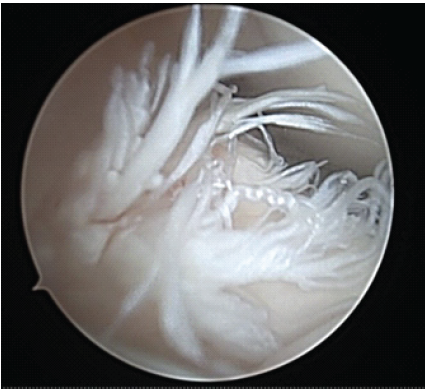

A 12-year-old and 1-month-old premenarchal female presented with a right knee injury after playing basketball when another player collided, striking the patient’s right knee on the outside. The patient sustained a valgus injury to her right knee and felt a pop, followed by pain described as 8 on a scale of 1–10. The patient could not continue playing sports. The pain was described as a dull aching pain, and the patient was unable to bear weight. Patient past medical history was significant for febrile seizures. Patient past surgical history is unremarkable. There were no known drug allergies. The patient did not take any medication. Family history was significant for previous ACL tears with reconstructions in both the mother and father by the senior author 20+ years ago. Physical examination revealed a young female, 60 inches tall and 126 pounds. Here blood pressure was 108/59 with a pulse rate of 90. Initially, the patient had an examination of the non-affected, left knee, which was noted to have no pain to palpation, full range of motion, and ligamentous stability to Lachman’s, posterior drawer, and collateral ligament testing. Next, the patient had an exam of the right knee, revealing knee effusion to visual inspection with tenderness at the lateral femoral condyle to palpation. The patient was guarding and lacked full extension. Lachman’s examination was positive. The patient had a limitation of flexion to 60° limited by pain. The posterior drawer and pivot shift tests were unable to be assessed secondary to pain. The collateral ligaments were stable, and the patient had no calf tenderness and was neurovascularly intact. Three-view radiographs of the right knee were obtained, which did not reveal evidence of fracture. The patient was placed in a knee immobilizer with crutches and was protected weight-bearing with crutches and no sports. Magnetic resonance imaging (MRI) of the right knee was completed 12 days after injury, revealing a complete ACL tear without associated fracture, bone bruise, meniscal tear, or other ligament injury noted. The patient underwent anterior tibial displacement measurement with the knee tester (KT) arthrometer, revealing 7 mm side-to-side difference between the non-involved, left leg (9 mm) and the involved leg, right leg (16 mm) at 30° of flexion. The patient and family had a review of MRI and KT results with very lengthy discussion regarding the risks and benefits of treatment options, including non-operative treatment, ACL repair, and the various types of ACL reconstruction. Due to patient’s young age, premenarchal status, and understanding of the demands required for ACL reconstruction since both parents had undergone ACL reconstruction themselves, the parents desired to proceed with ACL repair understanding that there were no guarantees on relief of pain or restoration of ligamentous healing and knee stability, and consent was obtained. Less than 4 weeks after the injury, the patient underwent ACL repair. The patient was seen in the pre-operative holding area, where she previously received a femoral nerve block. The patient had initials placed on her right knee. The patient was brought to the operating room (OR), where she underwent a general laryngeal mask airway. The patient was placed in a supine fashion on the operative table. The upper extremities and ulnar nerves were well-padded and protected. A tourniquet was applied to the right proximal thigh area. The patient was placed in a Stryker leg holder. No tourniquet was used. The left lower extremity was well-padded on a blanket and pillow. A time-out was performed with confirmation of antibiotics. We began by injecting respective anteromedial and anterolateral portal sites with 10 mL of 0.25% bupivacaine with epinephrine. The patient then had portals developed. The scope was inserted laterally. On entering, the patellofemoral joint appeared to be intact. The fat pad was debrided for visualization of the ACL midsubstance tear, with mop ends noted (Fig. 1).

Figure 1: Intraoperative arthroscopic image from the anterolateral portal of the right knee with 30° arthroscope showing mid-substance anterior cruciate ligament rupture. Note torn mop ends of tibial stump.